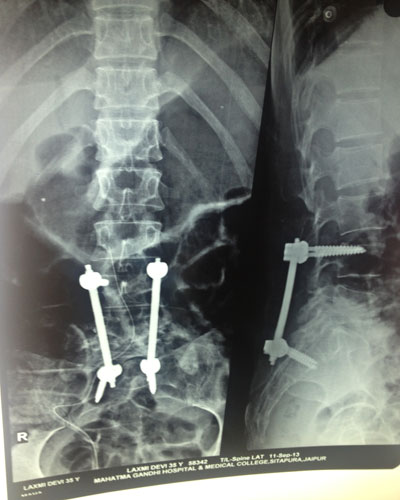

Surgery may be recommended if the conservative treatment options do not provide relief within two to three months. If leg or back pain limits normal activity, if there is weakness or numbness in the legs, if it is difficult to walk or stand, or if medication or physical therapy is ineffective, surgery may be necessary, most often spinal fusion.